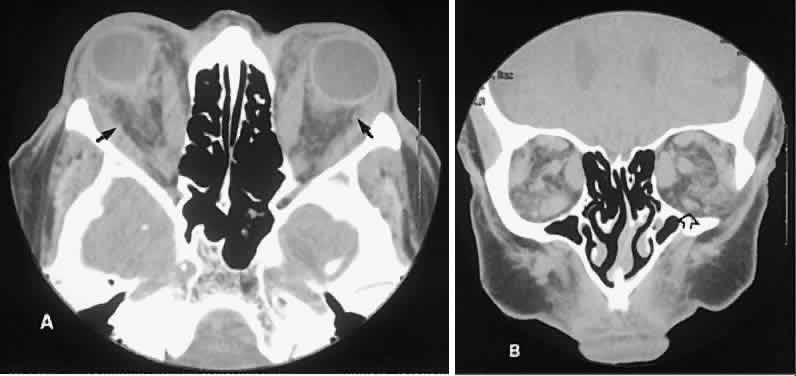

| Metastatic disease accounts for 2% to 10% of all orbital tumors.69,70 As a generalization, childhood metastases are from undifferentiated sarcomas, whereas

adult metastases are from postembryonal carcinomas. Radiographic evaluation can show either infiltrative or circumscribed masses. Some tumors display a predilection for metastasizing to certain structures, such as prostate carcinoma to bone and cutaneous melanoma to EOMs (Fig. 21). Evidence of bilateral disease at presentation ranges from 7% to 9%, with the prime example being neuroblastoma.71 |